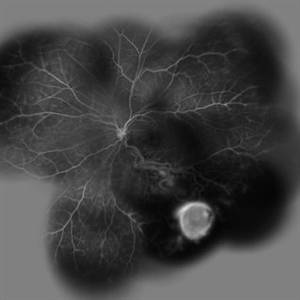

Von Hippel-Lindau Von Hippel-LindauSep 1 2014 by Hamid Ahmadieh, MD Two small retinal capillary hemangiomas detected by wide field FA in the symptom-free right eye of 30-year-old woman with Von Hippel-Lindau. Photographer: Solmaz Shahmohammad, Negah Eye Center, Tehran, Iran Condition/keywords: retinal capillary hemangioma, Von Hippel-Lindau